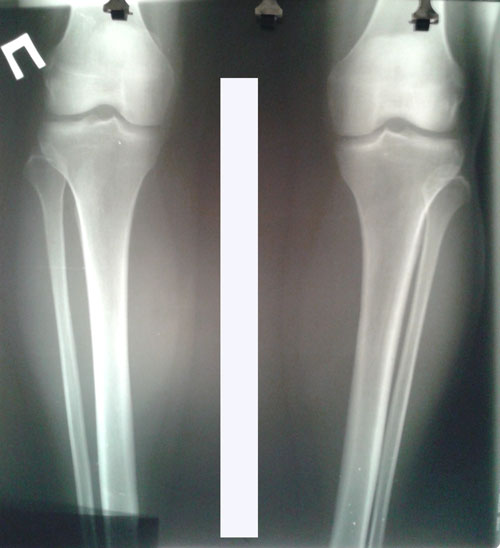

Рентген в 62 дня.

Сращение идёт отлично для этого срока и возраста пациентки.